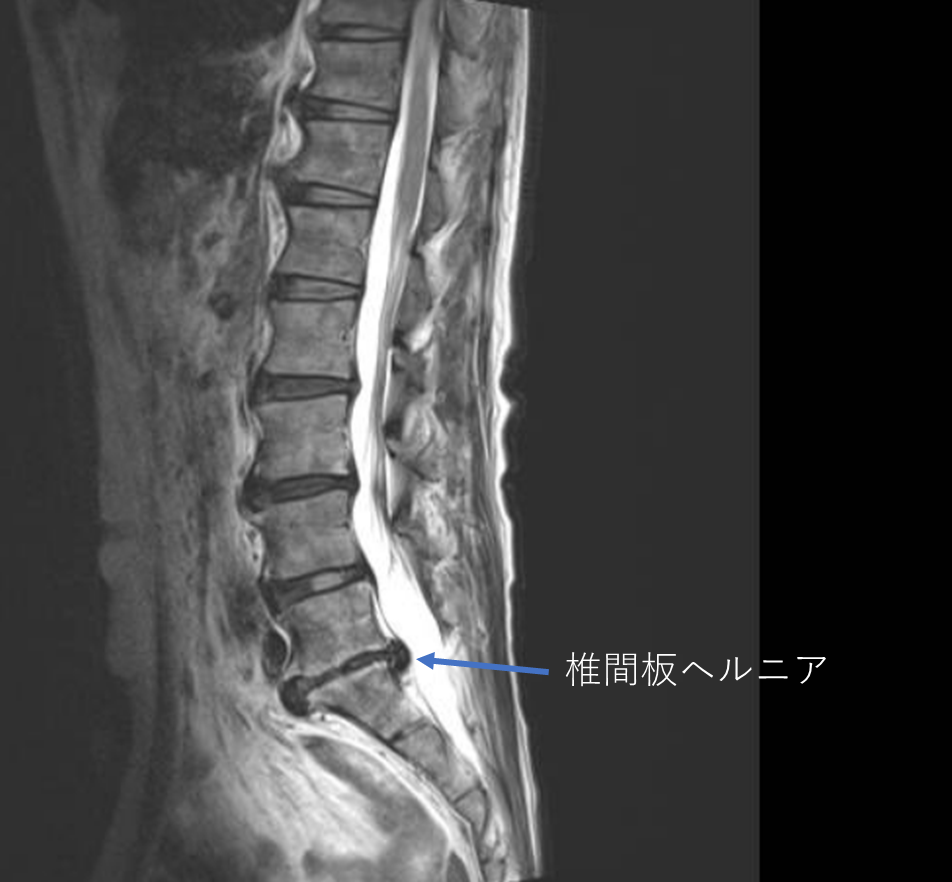

画像及び所見について

- L2/3,3/4,4/5,5/s-椎間板変性

- L5/s-椎間板ヘルニア

- L4/5-線維輪断裂

以上の事が画像上認められます。

・L4/5-椎間板変性による線維輪断裂を認め、予防的側面から

・L5/s-椎間板ヘルニアを認め、主症状の原因の可能性が高い